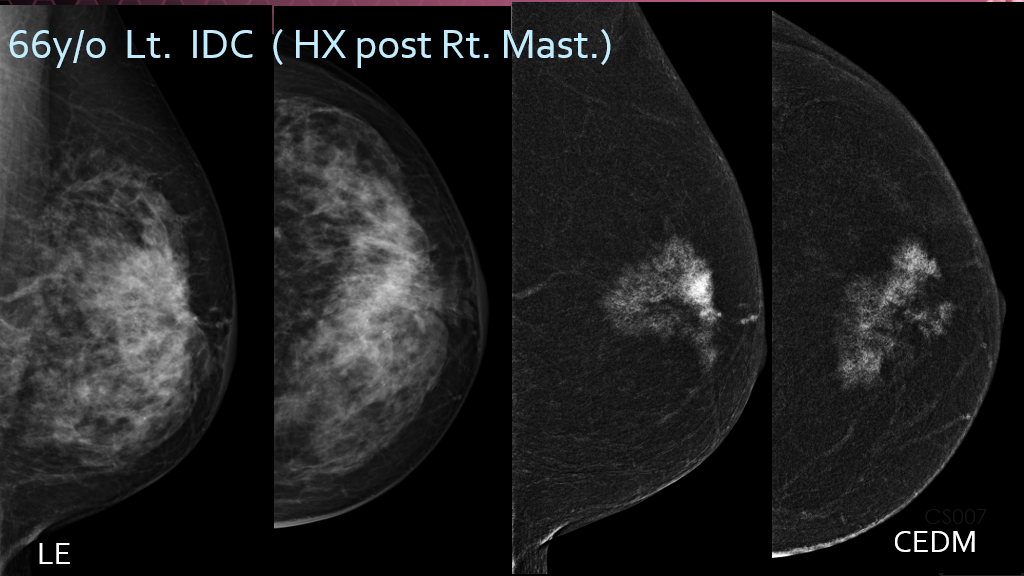

Shown here is a side-by-side comparison of conventional low energy imaging (left photos) vs. CEDM imaging (right photos) of an Invasive Ductal Carcinoma in a 66-year-old patient with dense breasts. You can see in the conventional imaging the cancer cannot be seen very well, but in the CEDM imaging it is quite evident.

By combining digital mammography with the administration of intravenous contrast material, CEDM enhances visualization of lesions that might otherwise be obscured. Clinical studies show that CEDM can detect additional cancers not seen on conventional mammograms, particularly in women with dense breasts. By better differentiating cancerous tissue from normal dense breast tissue, CEDM can potentially lower the rate of unnecessary biopsies from benign findings, or “false positives.”